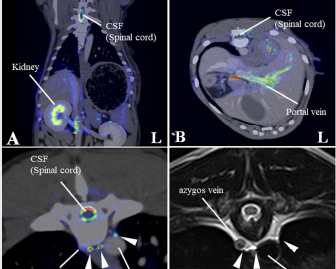

Fig. 2. Merged images from magnetic resonance thoracic ductography (MRTD) and contrast enhancement CT. The spinal cord, kidney, hepatic vein, aorta and portal vein were used as indices of the superpose method (A, B, C). The number of thoracic ducts at each vertebra between C5-L2 were recorded in transverse MRTD (C) and transverse T2-weighted image (D). (A) Fused image of the dorsal plane. (B) Fused image of the transverse plane. (C) Fused image of the transverse plane at the level of T7. Contrast enhancement CT image (monochrome); MRTD (rainbow). (D) T2-weighted image of the transverse plane at the level of T7. CSF: cerebrospinal fluid, white arrows (thoracic duct).

The raw MRI and CT data were transferred to a workstation (VAZE: PetCommunications, Chuo, Osaka, Japan) to construct the 3D images. In the MRTD images, the cerebrospinal fluid, pleura, kidney (renal pelvis) (Fig. 1A and C), part of the vessels (caudal vena cava, hepatic vein, and portal vein), and gastric juice were shown. Unnecessary fluids were removed in the maximum intensity projection (MIP) imaging of MRTD (Fig. 1B and D). Furthermore, 3D image of the thoracic duct was reconstructed from MRTD images, and 3D images of bone, heart, vessel, and esophagus were reconstructed from CT images. Those images were superposed using the “fusion” function on the workstation. The cerebrospinal fluid, kidney (renal pelvis), aorta, and liver vein (hepatic vein and portal vein) were used as indices of the superpose methods (Fig. 2A–C). The number of thoracic ducts at each vertebra between C5 andL2 were recorded in transverse MRTD (Fig. 2C) and T2WI (Fig. 2D). Location in relation to aorta and the location of the branches of thoracic duct were noted where possible. The comparison of the number of thoracic ducts at each vertebra between transverse T2WI and MRTD was performed using Student’s t-test. Statistical significance was set at p < 0.05.